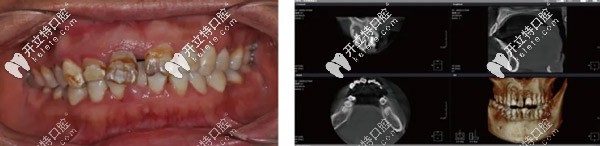

前牙美學(xué)區(qū)的種植修復(fù)要兼顧功能和美學(xué),所以對(duì)醫(yī)生的技術(shù)、種植體及基臺(tái)的選擇也比較嚴(yán)謹(jǐn)。下面,一起來(lái)看看前牙區(qū)用瑞士士卓曼Straumann? ITI Variobase AS基臺(tái)做即刻種植牙修復(fù)的案例吧!